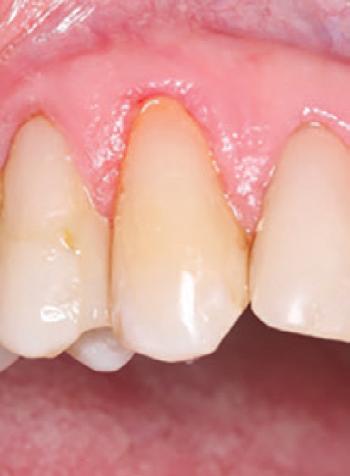

To improve isolation and soft tissue access, a retraction cord was placed before initiating the procedure (Fig. 2). The tooth was evaluated using a caries indicator dye (Kuraray Noritake Dental), helping to identify any remaining infected tissue beneath the dislodged composite (Fig. 3). Decay removal was completed with a diamond bur, and the enamel was bevelled using a starburst pattern to enhance aesthetic blending (Fig. 4). This preparation design was chosen for visual integration rather than bond strength enhancement.

2. Placement of retraction cord to improve isolation and access to the cervical area prior to preparation.